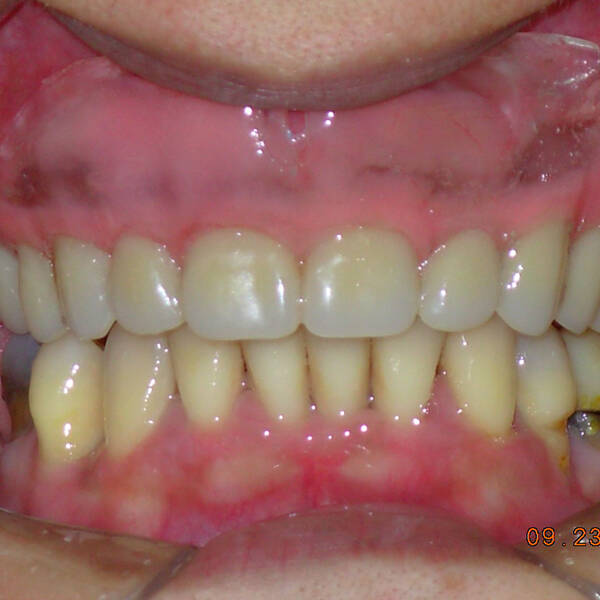

Na Clínica Pontes Odontologia, somos referência em implantes dentários em Fortaleza, oferecendo tratamentos de alta qualidade e tecnologia de ponta. Os implantes dentários são estruturas de titânio posicionadas cirurgicamente no osso maxilar ou mandibular para substituir as raízes dos dentes ausentes. Essa técnica permite a fixação de próteses personalizadas, restaurando a função mastigatória, a estética e a autoestima dos nossos pacientes.

Utilizamos a tecnologia CAD CAM, um sistema avançado que possibilita a confecção precisa das próteses dentárias diretamente sobre os implantes. Esse método inovador garante um ajuste perfeito, um resultado estético superior e proporciona muito mais conforto e durabilidade. Com o CAD CAM, nossos pacientes contam com um processo mais rápido e previsível para alcançar o sorriso desejado.